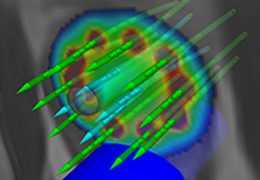

Diffusor Tension Imaging (DTI) module to analyze diffusion-weighted MRI data including calculation of FA maps, fiber tracking and FA group comparisons.

The surface reconstruction procedure starts with a sphere (recursively tesselated icosahedron) or a rectangle, which slowly wraps around a (segmented) volume data set. In order to avoid topological defects and to let the surface smoothly grow into deep sulci, a dynamic mesh algorithm was developed which automatically invents new polygons on the fly at places where they are needed. A reconstructed cortical surface may be inflated, cut interactively and slowly unfolded minimizing areal distortions. Statistical 3D maps may be superimposed on reconstructed, inflated or flattened cortex. Signal time courses may be invoked by simply pointing to any region of a visualized surface.